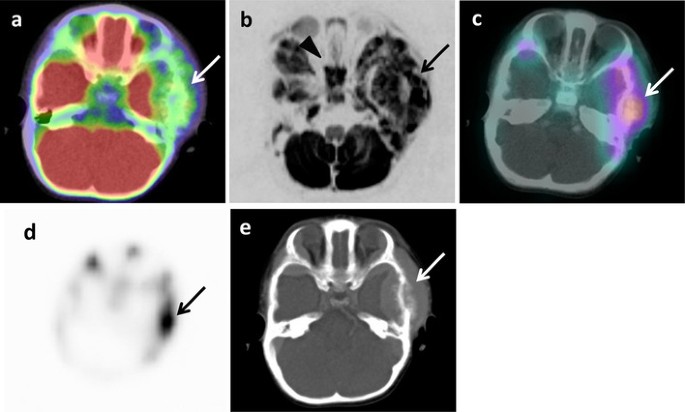

Fig. 2

Metastasis in left temporal bone of skull of 1 year and 7 months old girl (patient 6). a 18F-FDG PET/CT. b DWIBS. c 123I-MIBG scintigraphy/SPECT-CT. d Bone scintigraphy/SPECT. e CT. Arrows show metastasis (ae). Arrowhead shows false-positive images in sphenoidal bone (b)